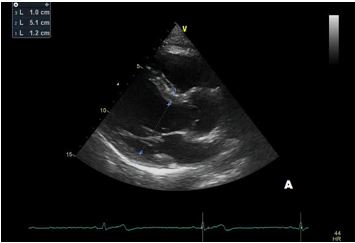

In our patient transthoracic echocardiography revealed normal diameters of the left ventricle with mild septal hypertrophy (EDD: 51 mm; ESD: 31 mm; IVS: 12 mm; PW 10 mm) with mild enlargement of the right ventricle (mid-cavity diameter: 37 mm), with normal biventricular systolic function. However, TTE revealed a tricuspid aortic valve with dilatation of the aortic root (44 mm, Z-score >2: Z=4.2). Ascending Aorta and aortic arch diameters were normal in absolute values (35 mm and 32 mm, respectively) and when keeping into consideration body size.

After a year, our patient underwent TTE that showed an aortic root dimension of 44 (Figure C), stable in comparison with the previous evaluation, with no modification of ascending aorta measurement and no LV enlargement (Figure A and B). He continues with yearly follow-up, continuing with personalized physical activity previously prescribed.